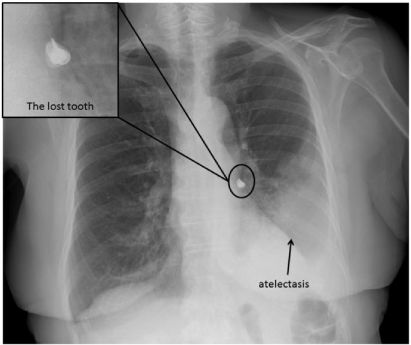

2017年3月底,广西省桂林市平乐县一位六旬老汉就在吃饭时被鱼刺卡了喉咙。他也是错误地采取了大口吞饭将鱼刺咽下的做法。到了第二天,这位姓赵的老汉胸部开始疼痛,第三天才到市人民医院就诊。

医生经过CT检查发现,鱼刺卡在了老赵的肺部,离大动脉仅剩2毫米远,并且已经引发轻微的肺部感染。如果再稍加一点刺激,鱼刺极大可能挑破大动脉。那就是会引起大出血的生命危险了。

最终,医生们当机立断在就诊当天完成手术取出鱼刺。只是老赵遭的这场罪,本可以通过正确的应急处理方式加上及时就医轻松化解的。